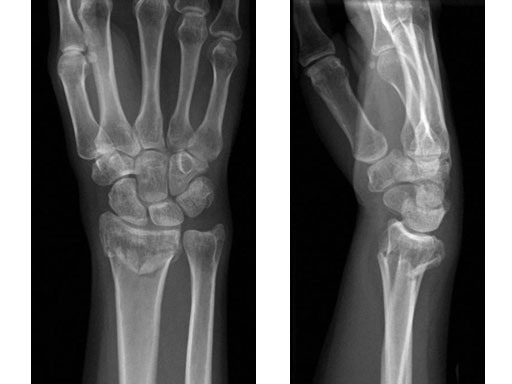

Fig 1ab Preoperative x-rays.

Fig 2ab X-rays postoperatively.